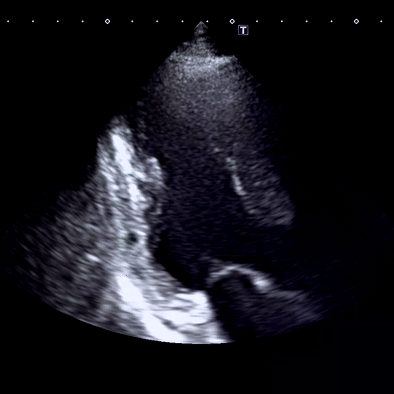

심장내과에서 가장 중요한 검사인 심장초음파 검사 결과

심장은 움직이기 때문에 움직임을 관찰하는 심장초음파가 매우 유용한 검사입니다.

심장 기저부 외측 벽에서 국소적인 벽운동 장애(심근경색 환자)

심장초음파